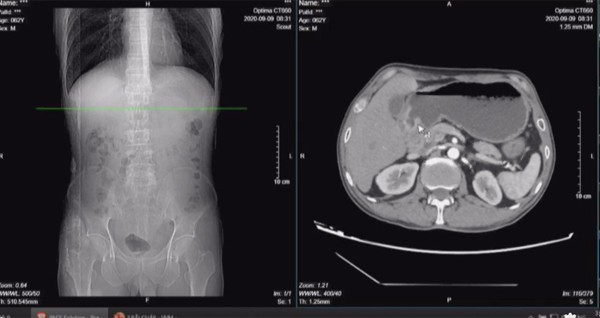

Ngày 7/9, ông được gia đình đưa vào Bệnh viện Bãi Cháy thăm khám. Các kết quả xét nghiệm và sinh thiết kết luận, bệnh nhân mắc ung thư hạ họng giai đoạn 4a thể biểu mô vảy và ung thư dạ dày biểu mô tuyến giai đoạn 2b thể kém biệt hoá, có biến chứng hẹp môn vị.

Trong đó ung thư hạ họng có khối u hơn 3,4 cm tại chỗ, xâm lấn vào dây thanh quản, ngoài ra đã di căn lan ra cơ ức đòn chũm, hạch lớn nhất hơn 2 cm.

TS Phạm Văn Bình, Trưởng khoa Ngoại bụng 1 nhận định, bệnh nhân xuất hiện 3 hạch 7 mm ở gần dạ dày và xếp giai đoạn 2 là chưa thực sự chuẩn. Để xác định chính xác có phải hạch di căn hay không cần mổ để sinh thiết vì kết quả chụp CT scanner có độ nhạy và độ đặc hiệu chỉ được 60-70%.